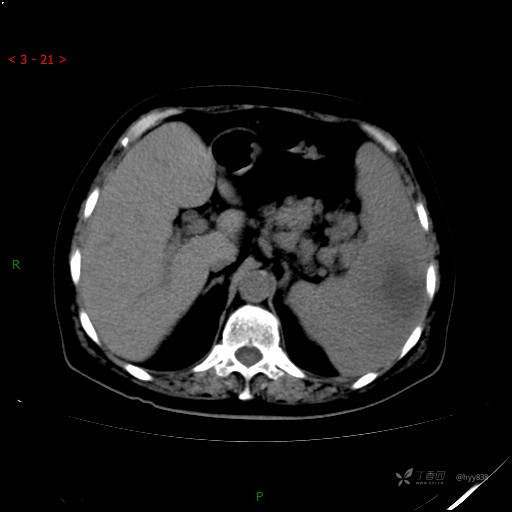

动脉期